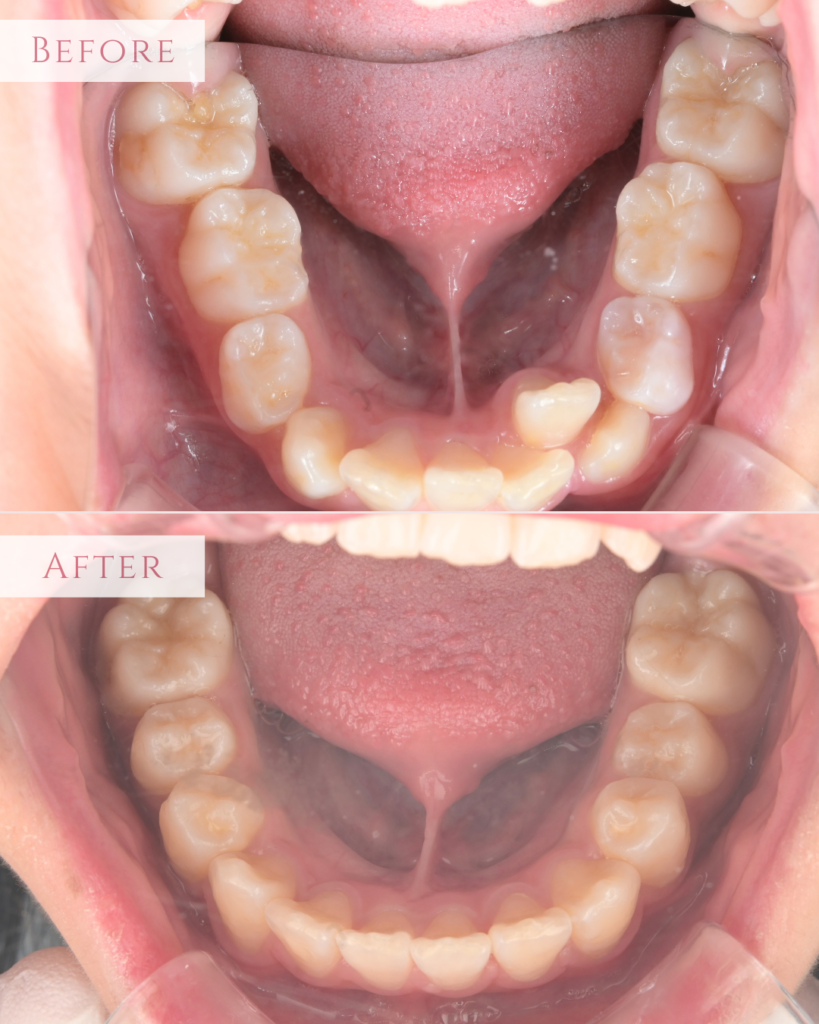

【5】下顎の咬合面

下顎も同様にスペースが不足し、前歯がガタガタ(叢生)していました。 治療後は、歯列が拡大されてスペースが生まれ、重なり合っていた前歯がきれいに並びました。